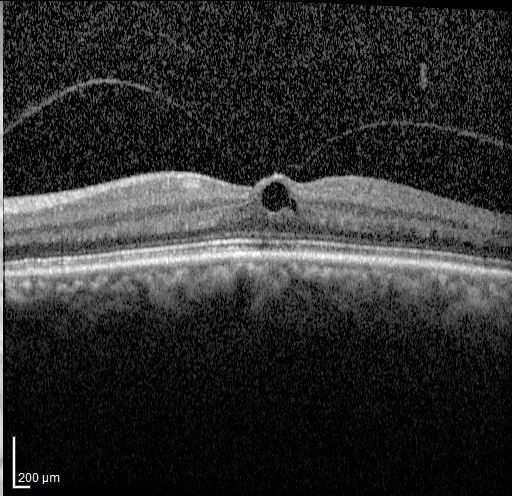

Optical coherence tomography image of a macular hole.

Macular Hole

Macular holes can cause central blur and distortion; surgery can restore vision.

• Macular hole OCT: Hanay. Source, CC BY-SA 3.0